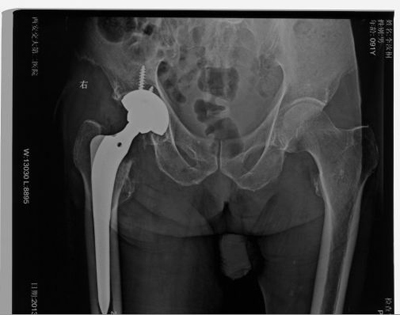

近日,我院骨一科成功为两位百岁超高龄老人施行了股骨颈骨折人工全髋关节置换术。患者术后均恢复良好,日前已康复出院并能拄拐行走。

经过谨慎细致的术前准备,在麻醉手术科的全力配合下,由王坤正主任主刀,宋金辉副教授主助,张晨主治医师、唐一仑主治医师配合,先后为两位患者施行了股骨颈骨折人工全髋关节置换术。手术历时均约1个小时,过程安全平稳顺利。手术后患者生命体征平稳,经抗炎、镇痛、对症支持治疗患者逐步康复。术后1周,患者由家属搀扶拄拐下地活动。患者及其家属对手术效果非常满意。

股骨颈骨折施行人工髋关节置换手术本身难度不大,但要为近百岁高龄的老人施行此类手术,不仅是对手术医师、麻醉医师的挑战,更是需要我院强大的医疗护理体系保障。我院骨一科在中华医学会骨科分会副主任委员兼关节外科学组组长王坤正主任的带领下,在人工髋关节置换领域(包括高龄患者股骨颈骨折、成人髋关节发育不良等高风险,复杂髋关节置换等)积累了丰富的经验。骨一科为超高龄患者成功施行人工髋关节置换手术成功突破了以往髋关节置换手术的超高龄禁区,为超高龄患者股骨颈骨折手术治疗带来了希望和福音,也标志着我院骨科及相关医护体系综合技术水平和整体实力上了一个新台阶。